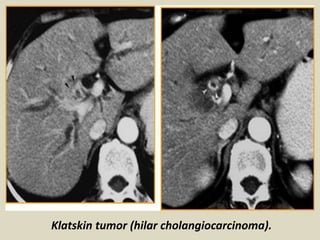

Hilar cholangiocarcinoma The most common

location for cholangiocarcinoma is either at the

confluence of the right and left hepatic ducts, or at

the proximal CHD, and has been termed a ''Klatskin

tumor.'' These tumors can be small and difficult to

visualize early at imaging. Hilar

cholangiocarcinoma can usually be differentiated

from adjacent adenopathy or extrinsic masses

causing biliary obstruction due to the latter

causing compression and displacement of the duct.

Occasionally large masses can envelope the biliary

tree, in which case the site of origin may be

difficult to determine.

Klatskin tumor (hilar cholangiocarcinoma).